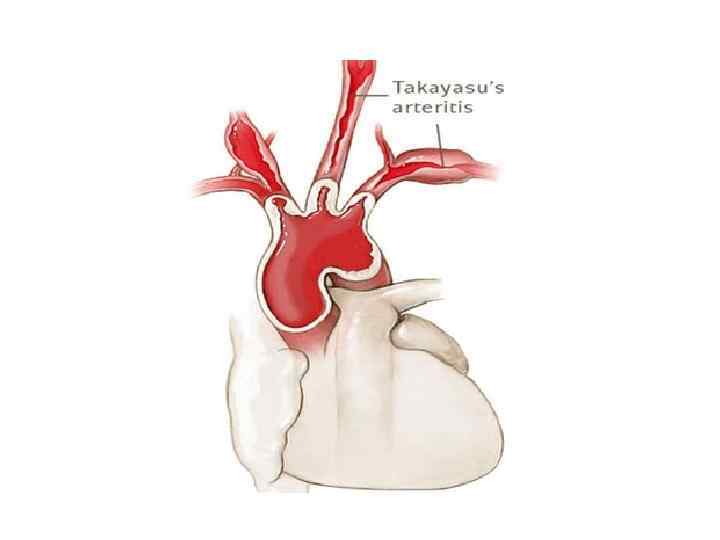

АОРТОАРТЕРИИТ ТАКАЯСУ 1. РАЗНИЦА НАПОЛНЕНИЯ ПУЛЬСА И АД НА РУКАХ 2. ЧАЩЕ СТРАДАЮТ ЖЕНЩИНЫ СРЕДНЕГО ВОЗРАСТА 3. ПРИЗНАКИ ВОСПАЛЕНИЯ (ПОВЫШЕНИЕ СОЭ, ЦРБ) 4. ДОППЛЕРОМЕТРИЯ ДЕМОНСТРИРУЕТ РАЗНИЦУ ОБЪЕМНОГО КРОВОТОКА

АОРТОАРТЕРИИТ ТАКАЯСУ 1. РАЗНИЦА НАПОЛНЕНИЯ ПУЛЬСА И АД НА РУКАХ 2. ЧАЩЕ СТРАДАЮТ ЖЕНЩИНЫ СРЕДНЕГО ВОЗРАСТА 3. ПРИЗНАКИ ВОСПАЛЕНИЯ (ПОВЫШЕНИЕ СОЭ, ЦРБ) 4. ДОППЛЕРОМЕТРИЯ ДЕМОНСТРИРУЕТ РАЗНИЦУ ОБЪЕМНОГО КРОВОТОКА